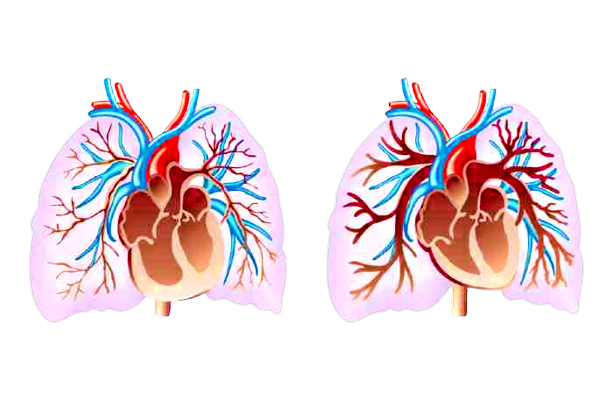

Impianto in arteria polmonare controlla cuore a distanza

Un dispositivo miniaturizzato di 14 millimetri di diametro è stato impiantato da medici dell’ospedale milanese di Niguarda in un ramo dell`arteria polmonare di un paziente residente a oltre 1.000 chilometri di distanza. È la soluzione che permette ai cardiologi di tenere sotto controllo giorno per giorno i valori di pressione polmonare del paziente che abita in Calabria. Il device è più piccolo di una moneta da 10 centesimi e si aggancia alle reti wi-fi circostanti o alla connessione dello smartphone per trasmettere i dati necessari per il monitoraggio a distanza.

“Il paziente è in cura a Niguarda dalla fine del 2021 per una cardiomiopatia dilatativa ed è stato messo in lista per trapianto cardiaco. Non se ne parla molto, ma questa condizione, lo scompenso cardiaco, interessa più di 1,2 milioni di italiani e ogni anno porta a 200.000 ricoveri in tutto il Paese – ha scritto in una nota Andrea Garascia, Direttore del reparto di Cardiologia 2 -. Un monitoraggio continuo e attento dei pazienti è la strada migliore per giocare d`anticipo ed evitare la fase acuta che porta a repentini peggioramenti con conseguenti accessi al pronto soccorso e ricoveri. Per questo motivo vista anche l`area di residenza del paziente il monitoraggio a distanza della pressione polmonare ci è sembrata la soluzione migliore per tenere sotto controllo la situazione con continuità”.

In questo modo eventuali anomalie registrate consentiranno ai medici milanesi di aggiustare il piano terapeutico del paziente calabrese, con l`obiettivo di tenere sotto controllo lo scompenso cardiaco e arrivare nelle migliori condizioni al trapianto di cuore. Il dispositivo grazie alle dimensioni contenute è stato impiantato con una procedura mininvasiva, veloce e condotta in anestesia locale. Il tutto si è completato nell`arco di 30-45 minuti e con il dispositivo in sede viene subito testata la funzionalità e la capacità di trasmissione dati. Il dispositivo è ampiamente utilizzato negli Stati Uniti, in Germania e in Francia mentre in Italia lo hanno adottato solo pochi centri. Niguarda è il primo ospedale pubblico a utilizzarlo in Regione Lombardia.